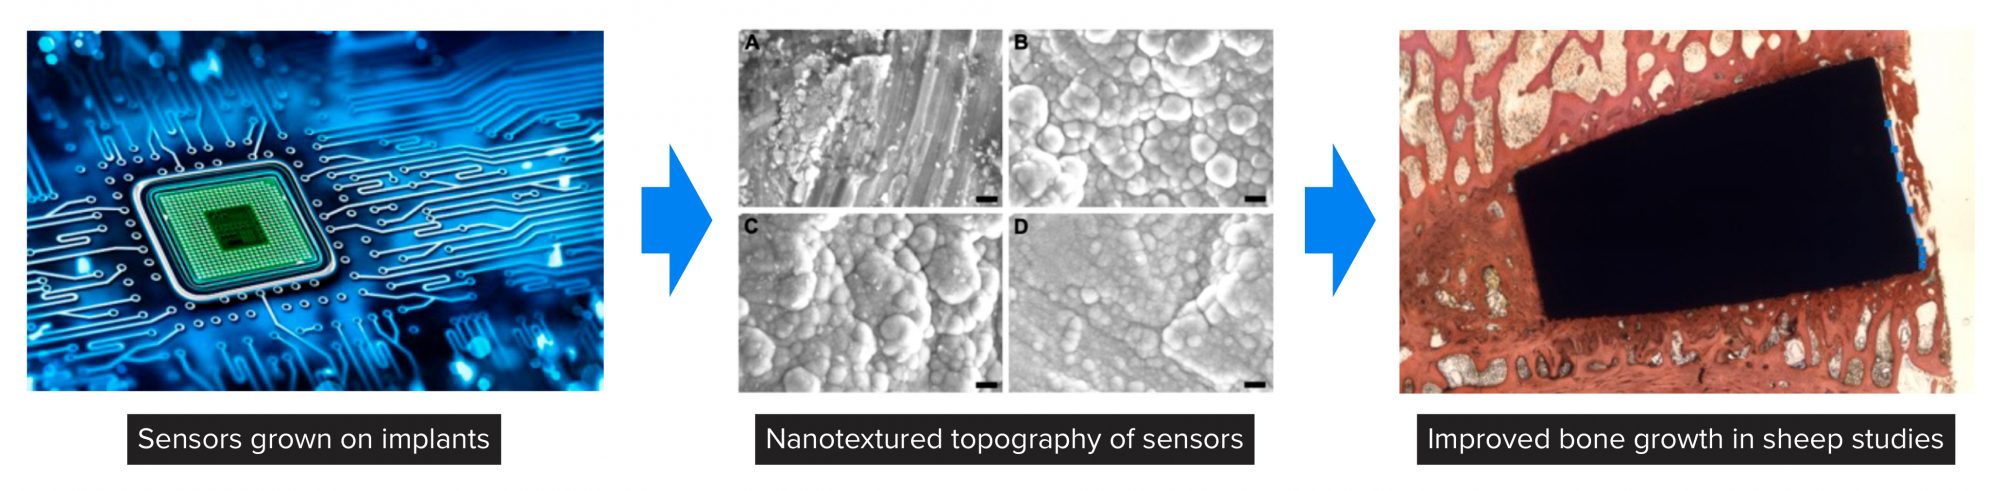

Figure 4 highlights Kalnar Technologies in which Professor Webster has used his expertise to grow sensors from implants and, by gathering information of what types of cells are attaching to implants in real-time, use AI to predict whether implant infection, chronic inflammation, or appropriate tissue growth will occur. Demonstrated in this figure is how such sensors can be created by atomic layer deposition (ALD) to possess a nanoscale topography to promote bone growth in the spine of sheep after 12 weeks.